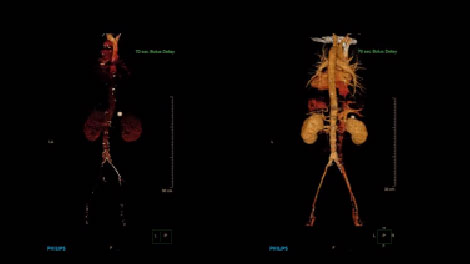

IQon Spectral CT добавляет спектральную информацию к стандартным КТ-данным благодаря новому двухслойному спектральному детектору. С помощью сцинтиллятора на основе иттрия детектор NanoPanel Prism одновременно определяет низко- и высокоэнергетические фотоны, что позволяет не только выполнять просмотр анатомических структур, но также применять цветовое обозначение требуемых структур для определения их вещественного состава.

В отличие от стандартных, изображения, полученные с помощью системы IQon Spectral CT, всегда несут спектральную информацию — для этого не требуется планирования специального режима исследования и дополнительных настроек. Таким образом, пользователь может выполнять анализ спектральных данных любого изображения в ретроспективном режиме с помощью различных инструментов просмотра. К примеру, всегда можно выбрать моноэнергетический уровень или вычленить данные о составе тканей. Попробуйте сами.